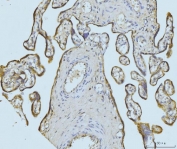

IHC staining of FFPE human placental tissue with ETFA antibody. HIER: boil tissue sections in pH8 EDTA for 20 min and allow to cool before testing.